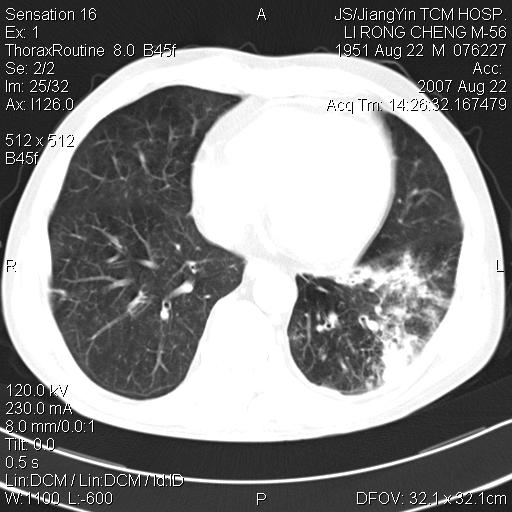

标题: CT9479:M,56Y,DM病史,咳嗽发热5天.肺脓疡.肺癌? [打印本页]

标题: CT9479:M,56Y,DM病史,咳嗽发热5天.肺脓疡.肺癌?

左肺下叶支气管呈小囊状扩张。下叶背段有类圆形高密度影,边缘模糊,外与胸膜相连。左侧胸膜增厚粘连。心包膜增厚。结合病史考虑1支扩并感染2胸膜及心包炎。

肺结核;肺内感染性变;支气管扩张;胸膜增厚。

考虑结核并支扩建议治疗后复查

支持肺脓肿,左下叶见广泛浸润,并见支扩改变。建议治疗后复查。

左肺下叶支扩合并感染,肺脓肿形成

但不除外结核。

支持:左下肺感染,脓肿形成,左下肺支气管扩张,左侧胸膜增厚。建议治疗复查,排除其他。